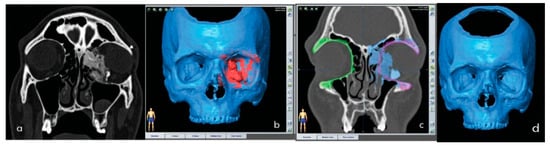

A 26-year-old male patient presented with a left endo-orbital mass associated with ocular bulb proptosis and diplopia. His medical history was negative for relevant chronic pathologies and he was not on any form of drug therapy. The physical examination highlighted the following: proptosis of the left eye, with upper-lateral dystopia of the ocular bulb (Figure 1), preserved extrinsic ocular movements, and diplopia. A CT scan showed an expansive mass (maximum diameter: 35 mm) with an irregular high-density structure suggestive of bone-like tissue. The mass, which originated in the wall of one of the posterior ethmoidal cells on the left, had an irregular morphology and lobate margins, extended to the medial wall of the left orbital cavity and occupied most of the medial and lower extraconal space. A small portion was insinuated between the medial and inferior rectus muscles. The tumor had benign radiological features and biopsy confirmed diagnosis. The ophthalmic and orthoptic evaluations, including a Hess-Lancaster test, showed no limitations in eye version and duction, a slight asymmetry of the palpebral fissures due to mild ptosis of the left eye and diplopia. Preoperative planning of the resection included the acquisition of a second CT scan with seven landmark points, necessary for surgical navigation [10]. Two titanium screws were placed in the patient’s upper orbital frame. In addition, an occlusal bite containing five screws was constructed for use during the CT scan [11,12]. Planning was performed using two software systems: iPlan 3.0 (Brainlab, Munich, Germany), for the mirroring process and surgical navigation, and PlastiCAD (3Diemme, Cantù, Italy), to virtually “subtract” the endo-orbital pathology (Figure 2a–d).

Figure 2. (a) CT scan showed an expansive mass, (b) orbital tumor, (c) the mirroring process, (d) to virtually “subtract” the endo-orbital pathology using PlastiCAD (3Diemme, Cantù, Italy).